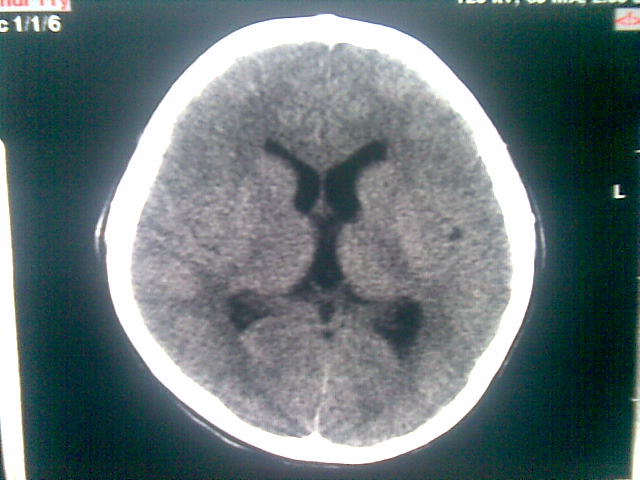

以下是引用随光逐影在2010-1-5 16:32:00的发言:[br]1)鞍上池囊性占位性病变,不排除蛛网膜囊肿可能;建议行mri检查。2)脑积水。

以下是引用yangyang2000在2010-1-5 20:41:00的发言:[br])鞍上池囊性占位性病变,不排除蛛网膜囊肿可能;建议行mri检查。2)脑积水

以下是引用yangyudong333在2010-1-5 21:28:00的发言:[br]1)鞍上池囊性占位性病变,不排除蛛网膜囊肿可能;建议行mri检查。2)脑积水。